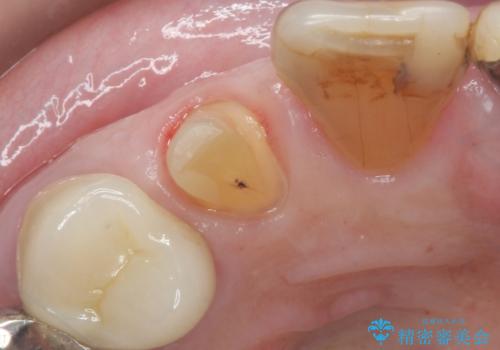

大きい虫歯で欠けた前歯 セラミッククラウンで治療

- 前歯が欠けたとのことで来院。

確認すると上の前歯の裏側に大きな虫歯がありました。

- 右上2 仮歯+ジルコニアクラウン(スタンダード) 11000円+110000円費用は治療当時の料金となります